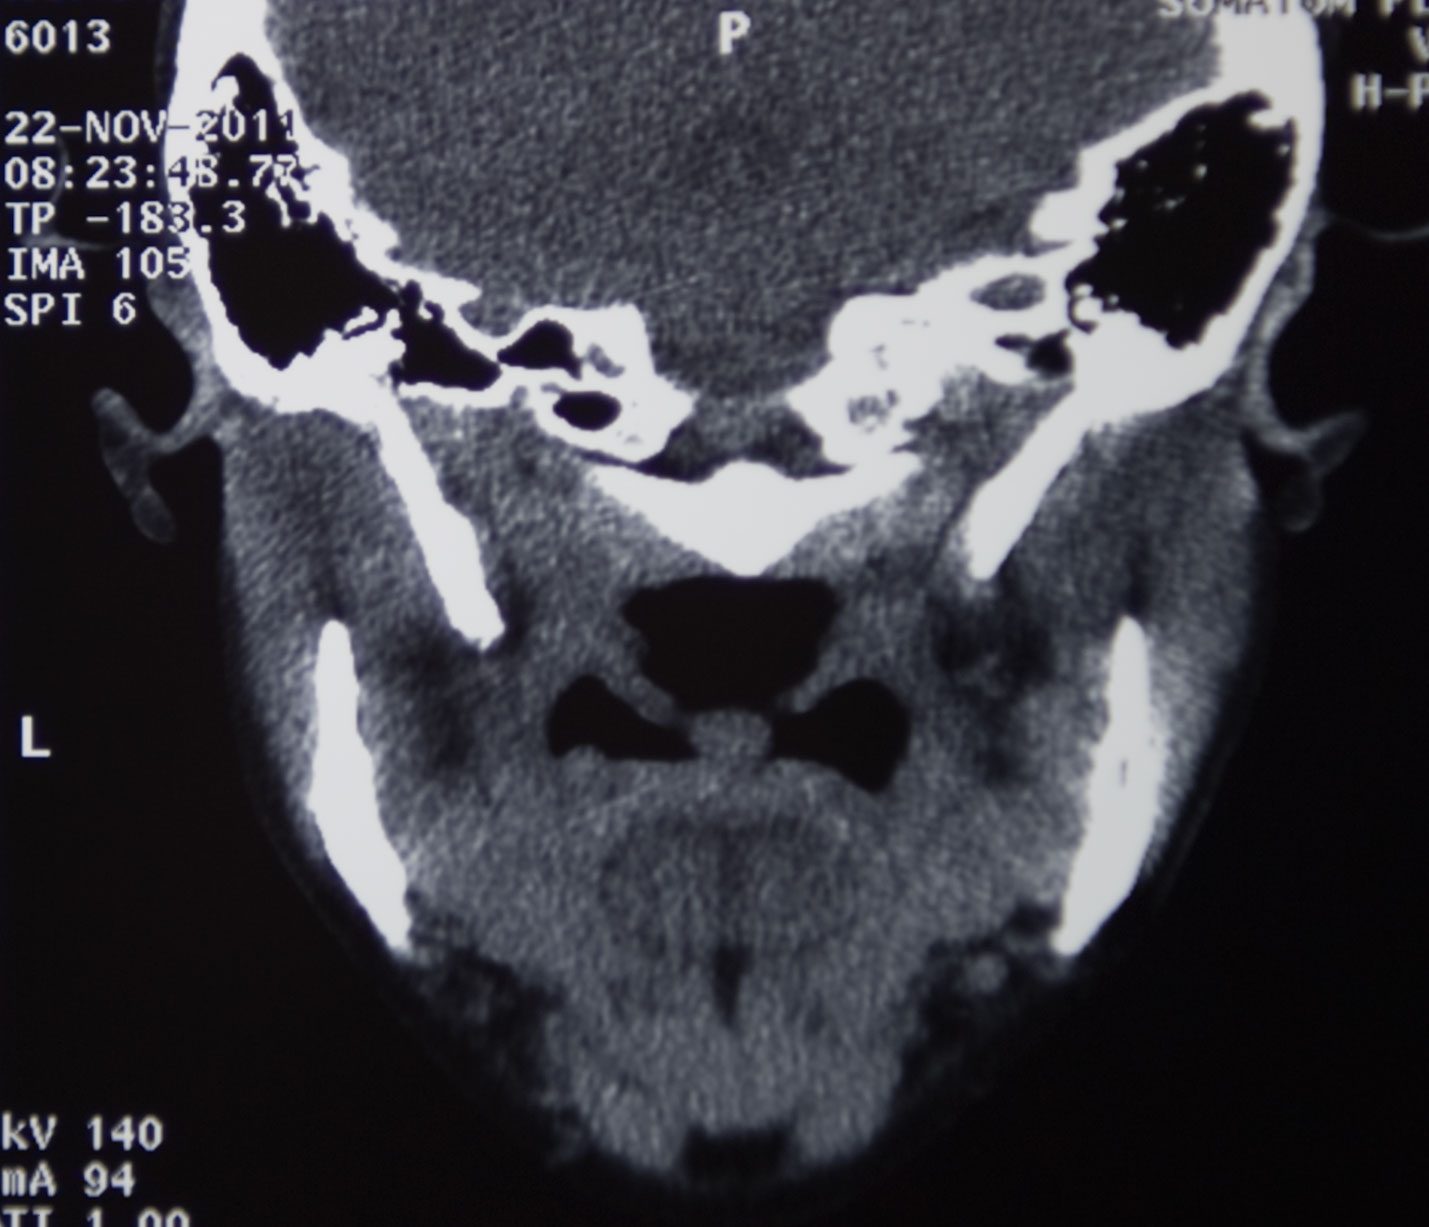

Arsović, Nenad